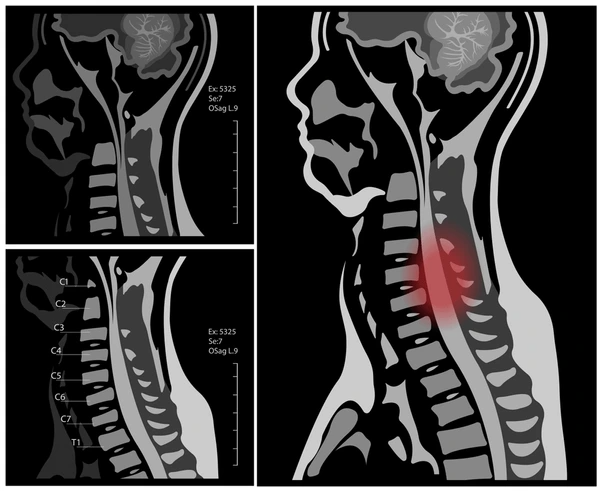

Cervical Spondylosis disease Image

• MRI or CT scans may be used to assess disc herniation, spinal cord compression, or nerve root involvement.